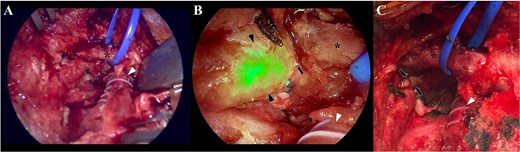

Under general anesthesia, re-exploration of the cervical site was carried out (Fig. 4). At the same time, under ultrasound guidance [8], a right inguinal lymphnode [8] was punctured with a 21G needle (Fig. 5) and the ICG was administered (0.2 mg/kg, 15 mg total) [9]. After 40 minutes, using a near-infrared camera (Hopkins® 0° NIR/ICG Optic, Storz. Tuttlingen, Germany; Fig. 6), a green bright structure was visualized. Direct and precise exploration of the lymphatic structure was carried out and the CL was identified and ligated (Fig. 7). After confirming no other CLs, the wound was closed leaving an aspirative drainage.

Forty minutes after the indocyanine green administration, the Hopkins® 0° NIR/ICG optic camera was directly situated and pointed into the surgical field.

Camera view of the surgical field, without the near-red feature (A), where is depicted the bypass (arrowhead) and the left jugular vein (asterisk). Two visible silk sutures from the previous intervention are also identified. With the near-red feature (B), the thoracic conduct is clearly visualized due to the presence of the indocyanine-green (black arrowheads). This allowed to precisely identify that the leak came from thoracic duct (black arrow), in an anatomical position near the bypass (white arrowhead) and the left jugular vein (asterisk). Once the leak was identified, a clip ligation was performed with a metallic clip (C; black arrows) and the incision was closed in a standard fashion.